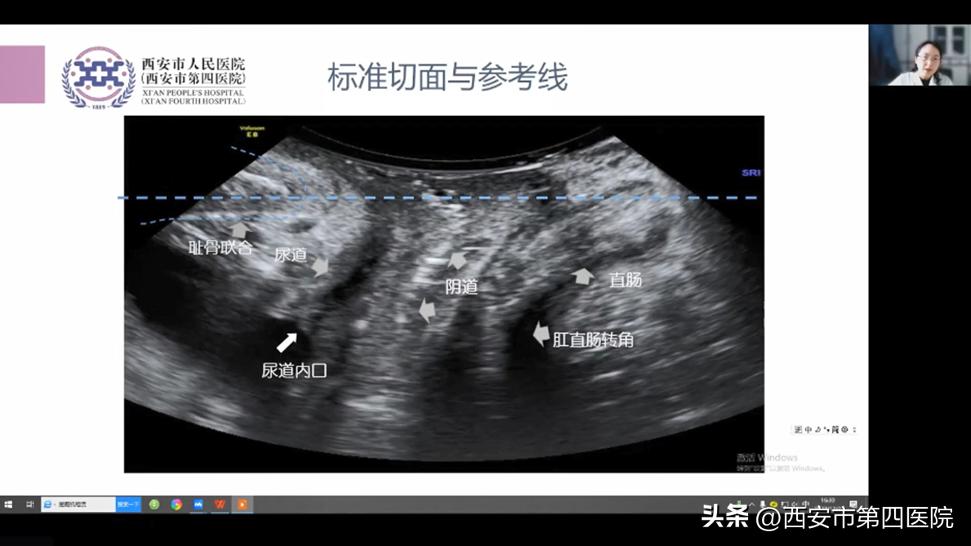

产后康复技术的发展与应用专场,特邀我院产后康复/盆底康复中心李丹副主任、范祎主任医师、黄文成教授、沈经国教授、欧洲生物反馈协会(BFE)讲师齐勤、张慧副主任、妇保中心王晓蕾医师,分别围绕产后盆底痛特点及临床诊疗思路、疼痛图谱的解读及临床应用、骨盆评估与矫正手法的应用、整脊在产后医学中的应用、“磁电联合”在产后的应用及进展、超声在盆底康复中的应用、营养与体重管理在产后康复中的应用等内容,进行了应用探讨。